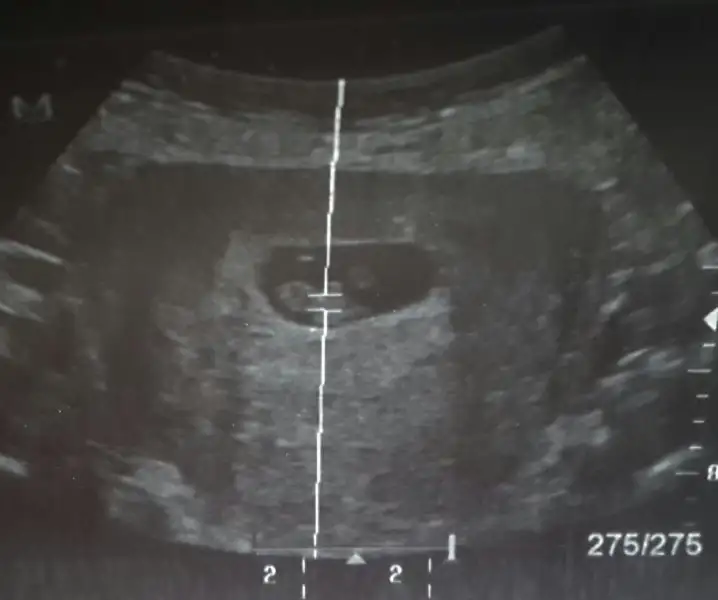

kızlar günaydın. benimkini de yorumlar mısnız? sat a göre 8+0 ama usg ye göre 8+5. teşekkürler şimdiden :) bu karından ultrason görüntüsü

Cnm ilk sayfada şöyle yazıyor;

Bu yöntem bircok kişide dogru sonuc verdii.

bebegin7-8 haftalıkkenki usg resimine direkt baktıgınızda;

bebek kesenin soluna yakınsa bebek erkek,

sagına yakınsa kız.

Senin bebek sola yakin,vajinal usg ile karından usg farklı.o yüzden seninki karındanmis bu teoriye erkek oluyor cnm.